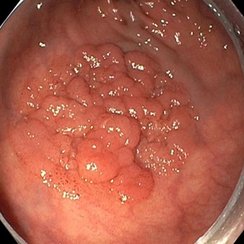

Eine Patientin stellte sich über unser Adipositaszentrum mehrere Jahre nach Magenbypass-Operation mit erneuter Gewichtszunahme und ausgeprägten Dumping-Beschwerden vor. In der Magenspiegelung zeigte sich eine deutlich erweiterte Anastomose.

Bild 1: Weit offene Anastomose vor der Behandlung